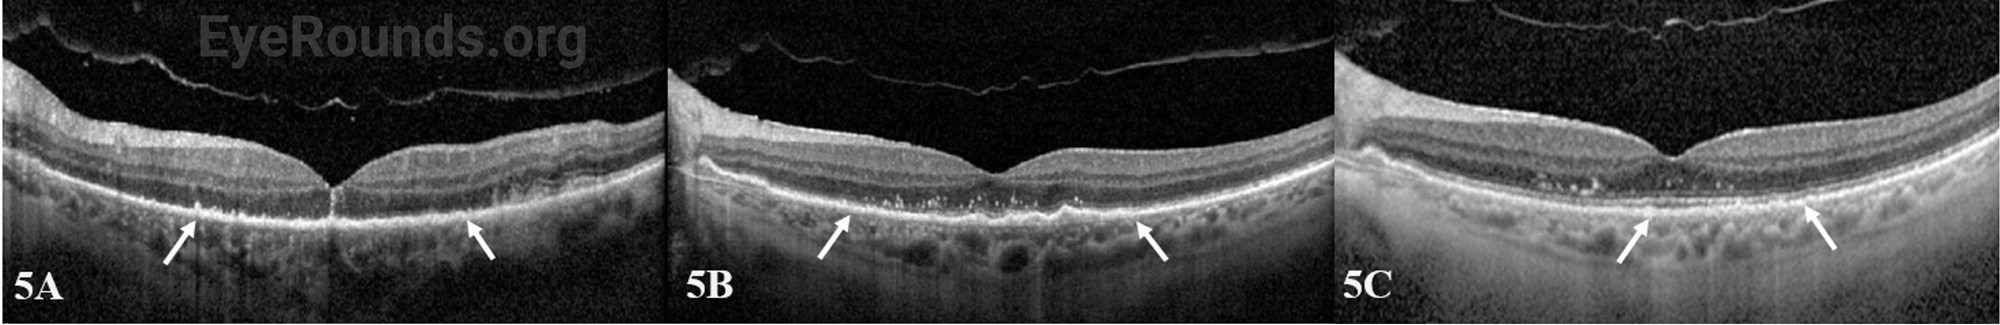

At one-week follow-up, the patient had improvement of his visual acuity to 20/400. Exam demonstrated interval improvement of the confluent areas of placoid whitening. Optical coherence tomography (OCT) of the left eye demonstrated early reconstitution of the outer retina and improvement of the subretinal hyper-reflective material. At 3-week follow-up, visual acuity improved to 20/50 with near resolution of the previously seen placoid whitening (Figure 4). There was residual outer retinal atrophy seen on OCT with early signs of reconstitution of outer retinal laminations (Figure 5B).

OCT macula of the left eye at the initial visit (A), 3-week follow-up (B), and 4-month follow-up (C)

Figure 5: OCT macula of the left eye at the initial visit (A), 3-week follow-up (B), and 4-month follow-up (C). At the initial visit there was prominent diffuse outer retinal atrophy through the macula involving the outer plexiform/nuclear layers with few small subretinal hyper-reflective deposits (arrows) (A). At the 3-week follow-up visit, there was persistent subretinal hyper-reflectivity with early reconstitution of the outer retinal laminations (B), which continued to improve at the 4-month follow-up visit (C).

At the 4-month follow-up clinic visit, the patient had further improvement of his visual acuity to 20/25, near complete resolution of the placoid whitening (Figure 6), and continued improvement in reconstitution of the outer retinal layers (Figure 5C).